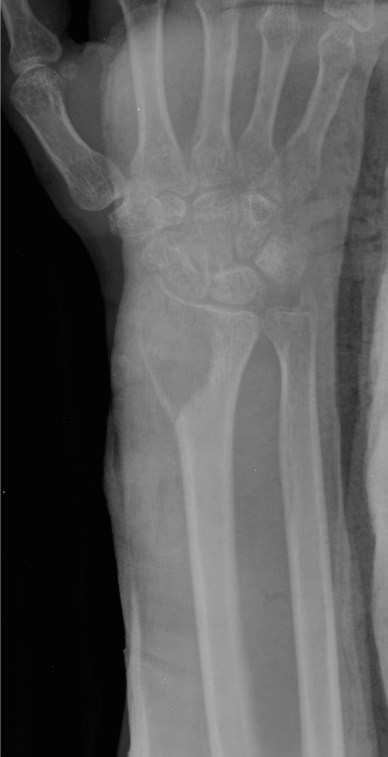

Case 2:

This is a frontal view of the wrist joint of a mature skeleton. (There is a cast present, indicating that the patient presented with fracture). There is mild soft tissue swelling. The fat planes are difficult to appreciate due to the overlying cast. There is a well defined osteolytic eccentric subarticular lesion in the distal radius with a narrow zone of transition. No periosteal reaction. Findings are consistent with giant cell tumor of the bone.